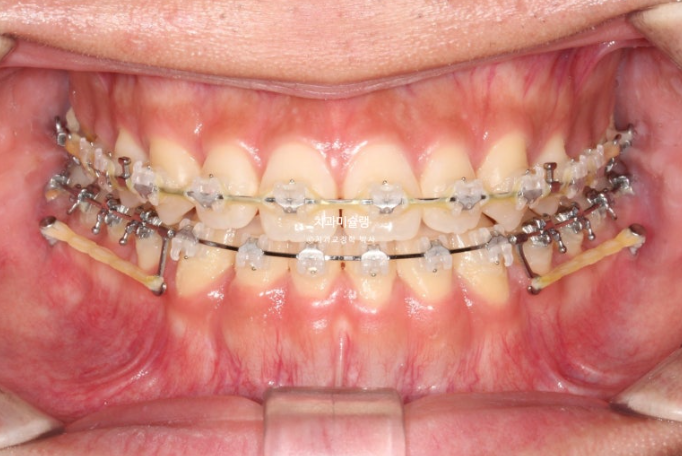

26.01

중심선은 정확히 맞으며 개방교합은 충분히 해소되었습니다.

반대교합은 개선되었고 교합관계는 1급을 달성